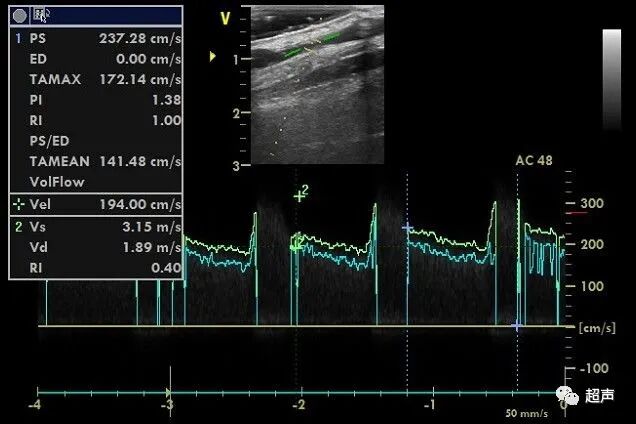

下图中,取样容积很小,血流频谱的宽度较小,结果容易偏高。

什么是超声容积探头血流量测定 |取样容积和角度θ_https://www.jmylbn.com_新闻资讯_第4张